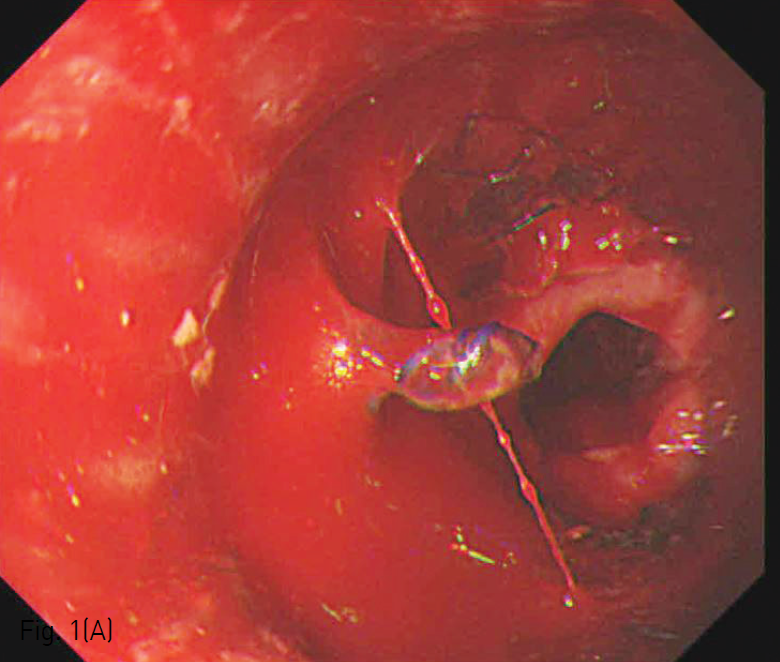

(A) Pseudoaneurysm and extravasation of contrast material into esophagus are seen in the aortogram.

(B) Pseudoaneurysm (arrow) and aortoesophageal fistula are still seen in the aortogram performed after stent graft was deployed in the thoracic aorta.

흉부외과와의 협진 하에 우측 총대퇴동맥을 절개하고, 좌측 총대퇴동맥은 초음파 유도하에 피부경유 천자법으로 접근하였다. 5-Fr sizing catheter를 왼쪽 총대퇴동맥을 통해 대동맥활에 위치시켰으며, 이를 통해 얻은 혈관조영영상에서 내림 흉부대동맥에서 기시하는 대동맥식도루를 통해 조영증강되는 식도 중부의 가성동맥류 및 식도 내부의 조영제 유출이 확인되었다(Fig. 2A). 흉부 컴퓨터단층촬영과 종합해 볼 때, 대동맥식도루는 왼쪽 빗장밑동맥(Left subclavian artery)으로부터 충분한 거리가 있었으며, 복강동맥으로부터도 충분한 거리가 있음을 확인할 수 있었다. 우측 총대퇴동맥을 통해 0.035”Guide wire (Radiofocus; Terumo, Tokyo, Japan)와 head-hunter type의 카테터(H1; Cook medical, Bloomington, IN, USA)를 오름 흉부대동맥에 위치시키고, extra-stiff guide wire (Lunderquist; Cook medical)으로 wire를 교체하였다. 이를 통해 24mmx6cm SEAL 흉부 스텐트 그라프트 (S&G Biotech, Sungnam-si, South Korea)을 진입시켰다. 이후 투시 하에 스텐트 그라프트를 왼쪽 빗장밑 동맥 원위부의 내림 흉부대동맥 내에서 설치하였다.

우측 천자부위의 스텐트 그라프트 운반기구를 제거한 뒤 시행한 혈관조영영상에서 아직 가성동맥류로의 조영제 유출이 있음을 확인하였고 (Fig. 2B), 이에 SEAL 풍선카테터 (S&G Biotech)을 이용하여 스텐트 그라프트를 혈관벽에 밀착시켰다 (Fig. 2C). 마지막 혈관조영영상에서 스텐트 그라프트는 충분히 늘어나있고 가성대동맥류는 혈류와 완전히 격리되었음을 확인하고 시술을 종료하였다 (Fig. 2D).